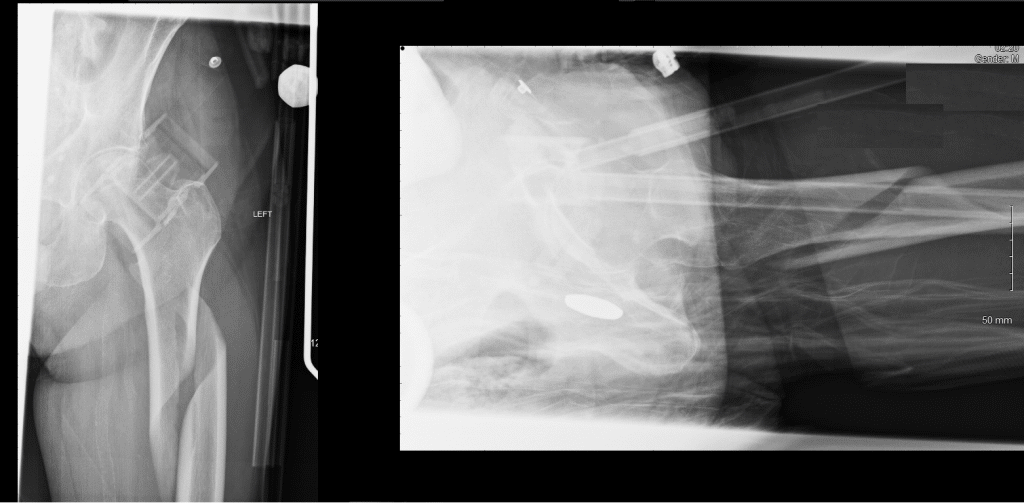

The femur is the only bone in the thigh and the longest bone in the body. It acts as the site of origin and attachment of many muscles and ligaments, and can be divided into three parts; proximal, shaft and distal. In this article, we shall look at the anatomy of the femur – its attachments, bony landmarks, and clinical correlations. Pro Feature - 3D Model You've Discovered a Pro Feature Access our 3D Model Library Explore, cut, dissect, annotate and manipulate our 3D models to visualise anatomy in a dynamic, interactive way. Learn More Proximal The proximal aspect of the femur articulates with the acetabulum of the pelvis to form the hip joint. It consists of a head and neck, and two bony processes – the greater and lesser trochanters. There are also two bony ridges connecting the two trochanters; the intertrochanteric line anteriorly and the trochanteric crest posteriorly. Head – articulates with the acetabulum of the pelvis to form the hip joint. It has a smooth surface, covered with articular cartilage (except for a small depression – the fovea – where ligamentum teres attaches). Neck – connects the head of the femur with the shaft. It is cylindrical, projecting in a superior and medial direction. It is set at an angle of approximately 135 degrees to the shaft. This angle of projection allows for an increased range of movement at the hip joint. Greater trochanter – the most lateral palpable projection of bone that originates from the anterior aspect, just lateral to the neck. It is the site of attachment for many of the muscles in the gluteal region, such as gluteus medius, gluteus minimus and piriformis. The vastus lateralis originates from this site. An avulsion fracture of the greater trochanter can occur as a result of forceful contraction of the gluteus medius. Lesser trochanter – smaller than the greater trochanter. It projects from the posteromedial side of the femur, just inferior to the neck-shaft junction. It is the site of attachment for iliopsoas (forceful contraction of which can cause an avulsion fracture of the lesser trochanter). Intertrochanteric line – a ridge of bone that runs in an inferomedial direction on the anterior surface of the femur, spanning between the two trochanters. After it passes the lesser trochanter on the posterior surface, it is known as the pectineal line. It is the site of attachment for the iliofemoral ligament (the strongest ligament of the hip joint). It also serves as the anterior attachment of the hip joint capsule. Intertrochanteric crest – like the intertrochanteric line, this is a ridge of bone that connects the two trochanters. It is located on the posterior surface of the femur. There is a rounded tubercle on its superior half called the quadrate tubercle; where quadratus femoris attaches. By TeachMeSeries Ltd (2025) Fig 1The anterior surface of the proximal right femur. By TeachMeSeries Ltd (2025) Fig 2The posterior surface of the right femur. Clinical Relevance Proximal Femur Fractures Neck of femur fractures (NOFs) are increasingly common and tend to be sustained by the elderly population as a result of low energy falls in the presence of osteoporotic bone. They are more prevalent in women. In younger patients they tend to occur as a result of high energy accidents. The distal fragment is typically pulled upwards and rotated laterally. This manifests clinically as a shortened and externally rotated lower limb. These fractures can be broadly classified into two main groups: Intracapsular – occurs within the capsule of the hip joint. It can damage the medial femoral circumflex artery – and cause avascular necrosis of the femoral head. Extracapsular – the blood supply to the head of femur is intact, so avascular necrosis is a rare complication. The Shaft The shaft of the femur descends in a slight medial direction. This brings the knees closer to the body’s centre of gravity, increasing stability. A cross section of the shaft in the middle is circular but flattened posteriorly at the proximal and distal aspects. On the posterior surface of the femoral shaft, there are roughened ridges of bone, called the linea aspera (Latin for rough line). This splits distally to form the medial and lateral supracondylar lines. The flat popliteal surface lies between them. Proximally, the medial border of the linea aspera becomes the pectineal line. The lateral border becomes the gluteal tuberosity, where the gluteus maximus attaches. Distally, the linea aspera widens and forms the floor of the popliteal fossa, the medial and lateral borders form the medial and lateral supracondylar lines. The medial supracondylar line ends at the adductor tubercle, where the adductor magnus attaches. By TeachMeSeries Ltd (2025) Fig 3Posterior surface of the right femoral shaft. Clinical Relevance Fractures of the Femoral Shaft Fractures of the femoral shaft are typically a high energy injury but can occur in the elderly as a result of a low energy fall. They can often occur as a spiral fracture, which causes leg shortening. The loss of leg length is due the bony fragments overriding, pulled by their attached muscles. As the method of injury is typically high energy, the surrounding soft tissues may also be damaged. Neurovascular structures at risk include the femoral nerve and artery. A closed femoral shaft fracture may result in considerable haemorrhage (1000-1500ml) By TeachMeSeries Ltd (2025) Fig 4Spiral fracture of the femoral shaft. Distal The distal end of the femur is characterised by the presence of the medial and lateral condyles, which articulate with the tibia and patella to form the knee joint. Medial and lateral condyles – rounded areas at the end of the femur. The posterior and inferior surfaces articulate with the tibia and menisci of the knee, while the anterior surface articulates with the patella. The more prominent lateral condyle helps prevent the natural lateral movement of the patella; a flatter condyle is more likely to result in patellar dislocation. Medial and lateral epicondyles – bony elevations on the non-articular areas of the condyles. The medial epicondyle is the larger. The medial and lateral collateral ligaments of the knee originate from their respective epicondyles. Intercondylar fossa – a deep notch on the posterior surface of the femur, between the two condyles. It contains two facets for attachment of intracapsular knee ligaments; the anterior cruciate ligament (ACL) attaches to the medial aspect of the lateral condyle and the posterior cruciate ligament (PCL) to the lateral aspect of the medial condyle. By TeachMeSeries Ltd (2025) Fig 5Anterior surface of the distal right femur. By TeachMeSeries Ltd (2025) Fig 6Posterior surface of the distal right femur. Do you think you’re ready? Take the quiz below Pro Feature - Quiz The Femur Question 1 of 3 Submitting... Skip Next Rate question: You scored 0% Skipped: 0/3 1800 More Questions Available Upgrade to TeachMeAnatomy Pro Challenge yourself with over 1800 multiple-choice questions to reinforce learning Learn More Rate This Article